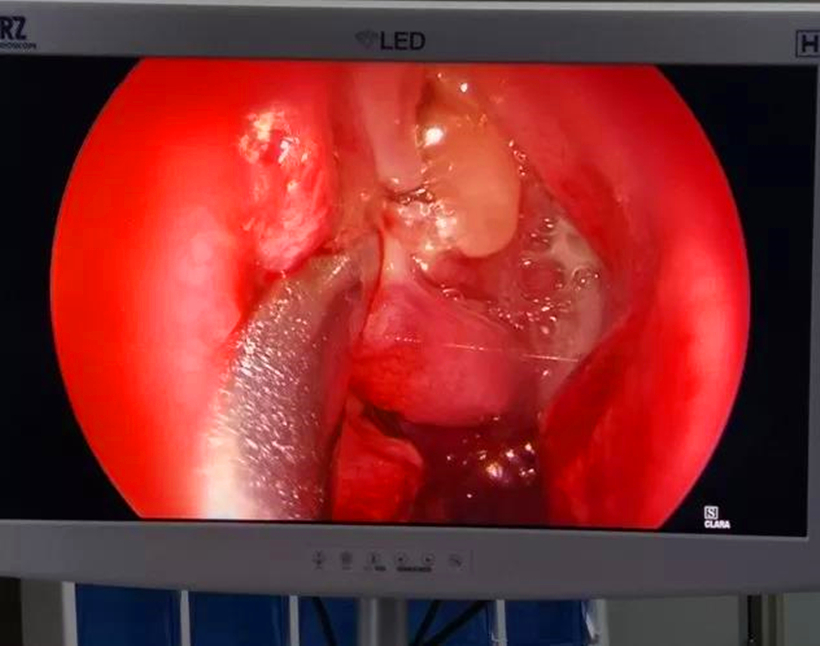

昆钢医院眼耳鼻喉科的医务人员在将患者推进入手术室,医生在鼻内镜的引导下,精心操作可降解鼻窦支架,随着一个白色网状物在筛窦口缓缓撑开,患者手术成功。可降解鼻窦支架可以起到物理支撑作用能够解决FESS术后中鼻甲漂移和术后严重粘连发生;手术结束后即刻植入支架,能够***时间精准、低剂量有效给药;支架涂层药物652μg,能够减少口服激素的使用量,提高患者用药安全性,术后三个月完全降解,无需再次手术取出,既减轻了患者的痛苦,又节约了复查换药时间,提高了患者的依从性,减少术后再次干预,大大增强了手术效果。